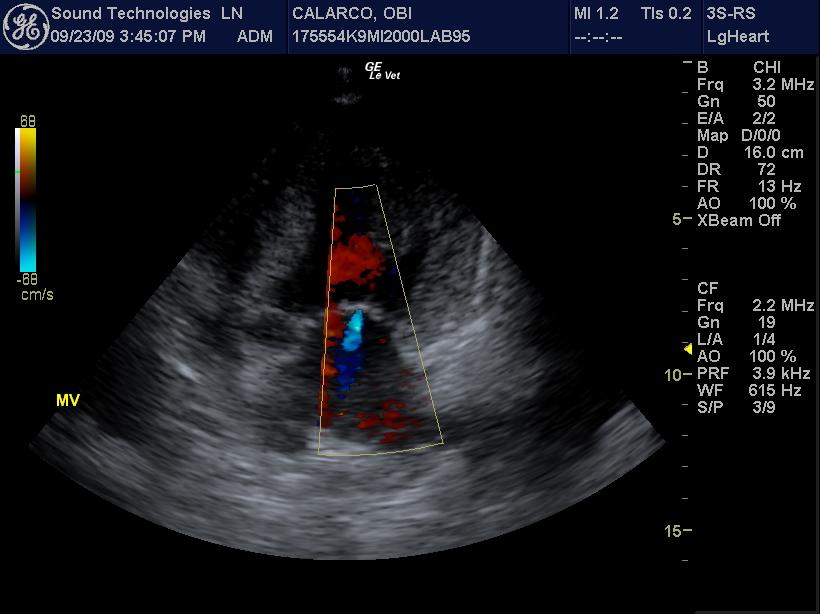

An 11-year-old MN Labrador retriever was prestented for excercise intolerance, lethargy, depression, vomiting and diarrhea. The physical exam was unremarkable other than a grade 2 left sided heart mumur at the heart base and irregular heart beat with pulse deficits. CBC, CHEM, UA, and acth stim were all normal.